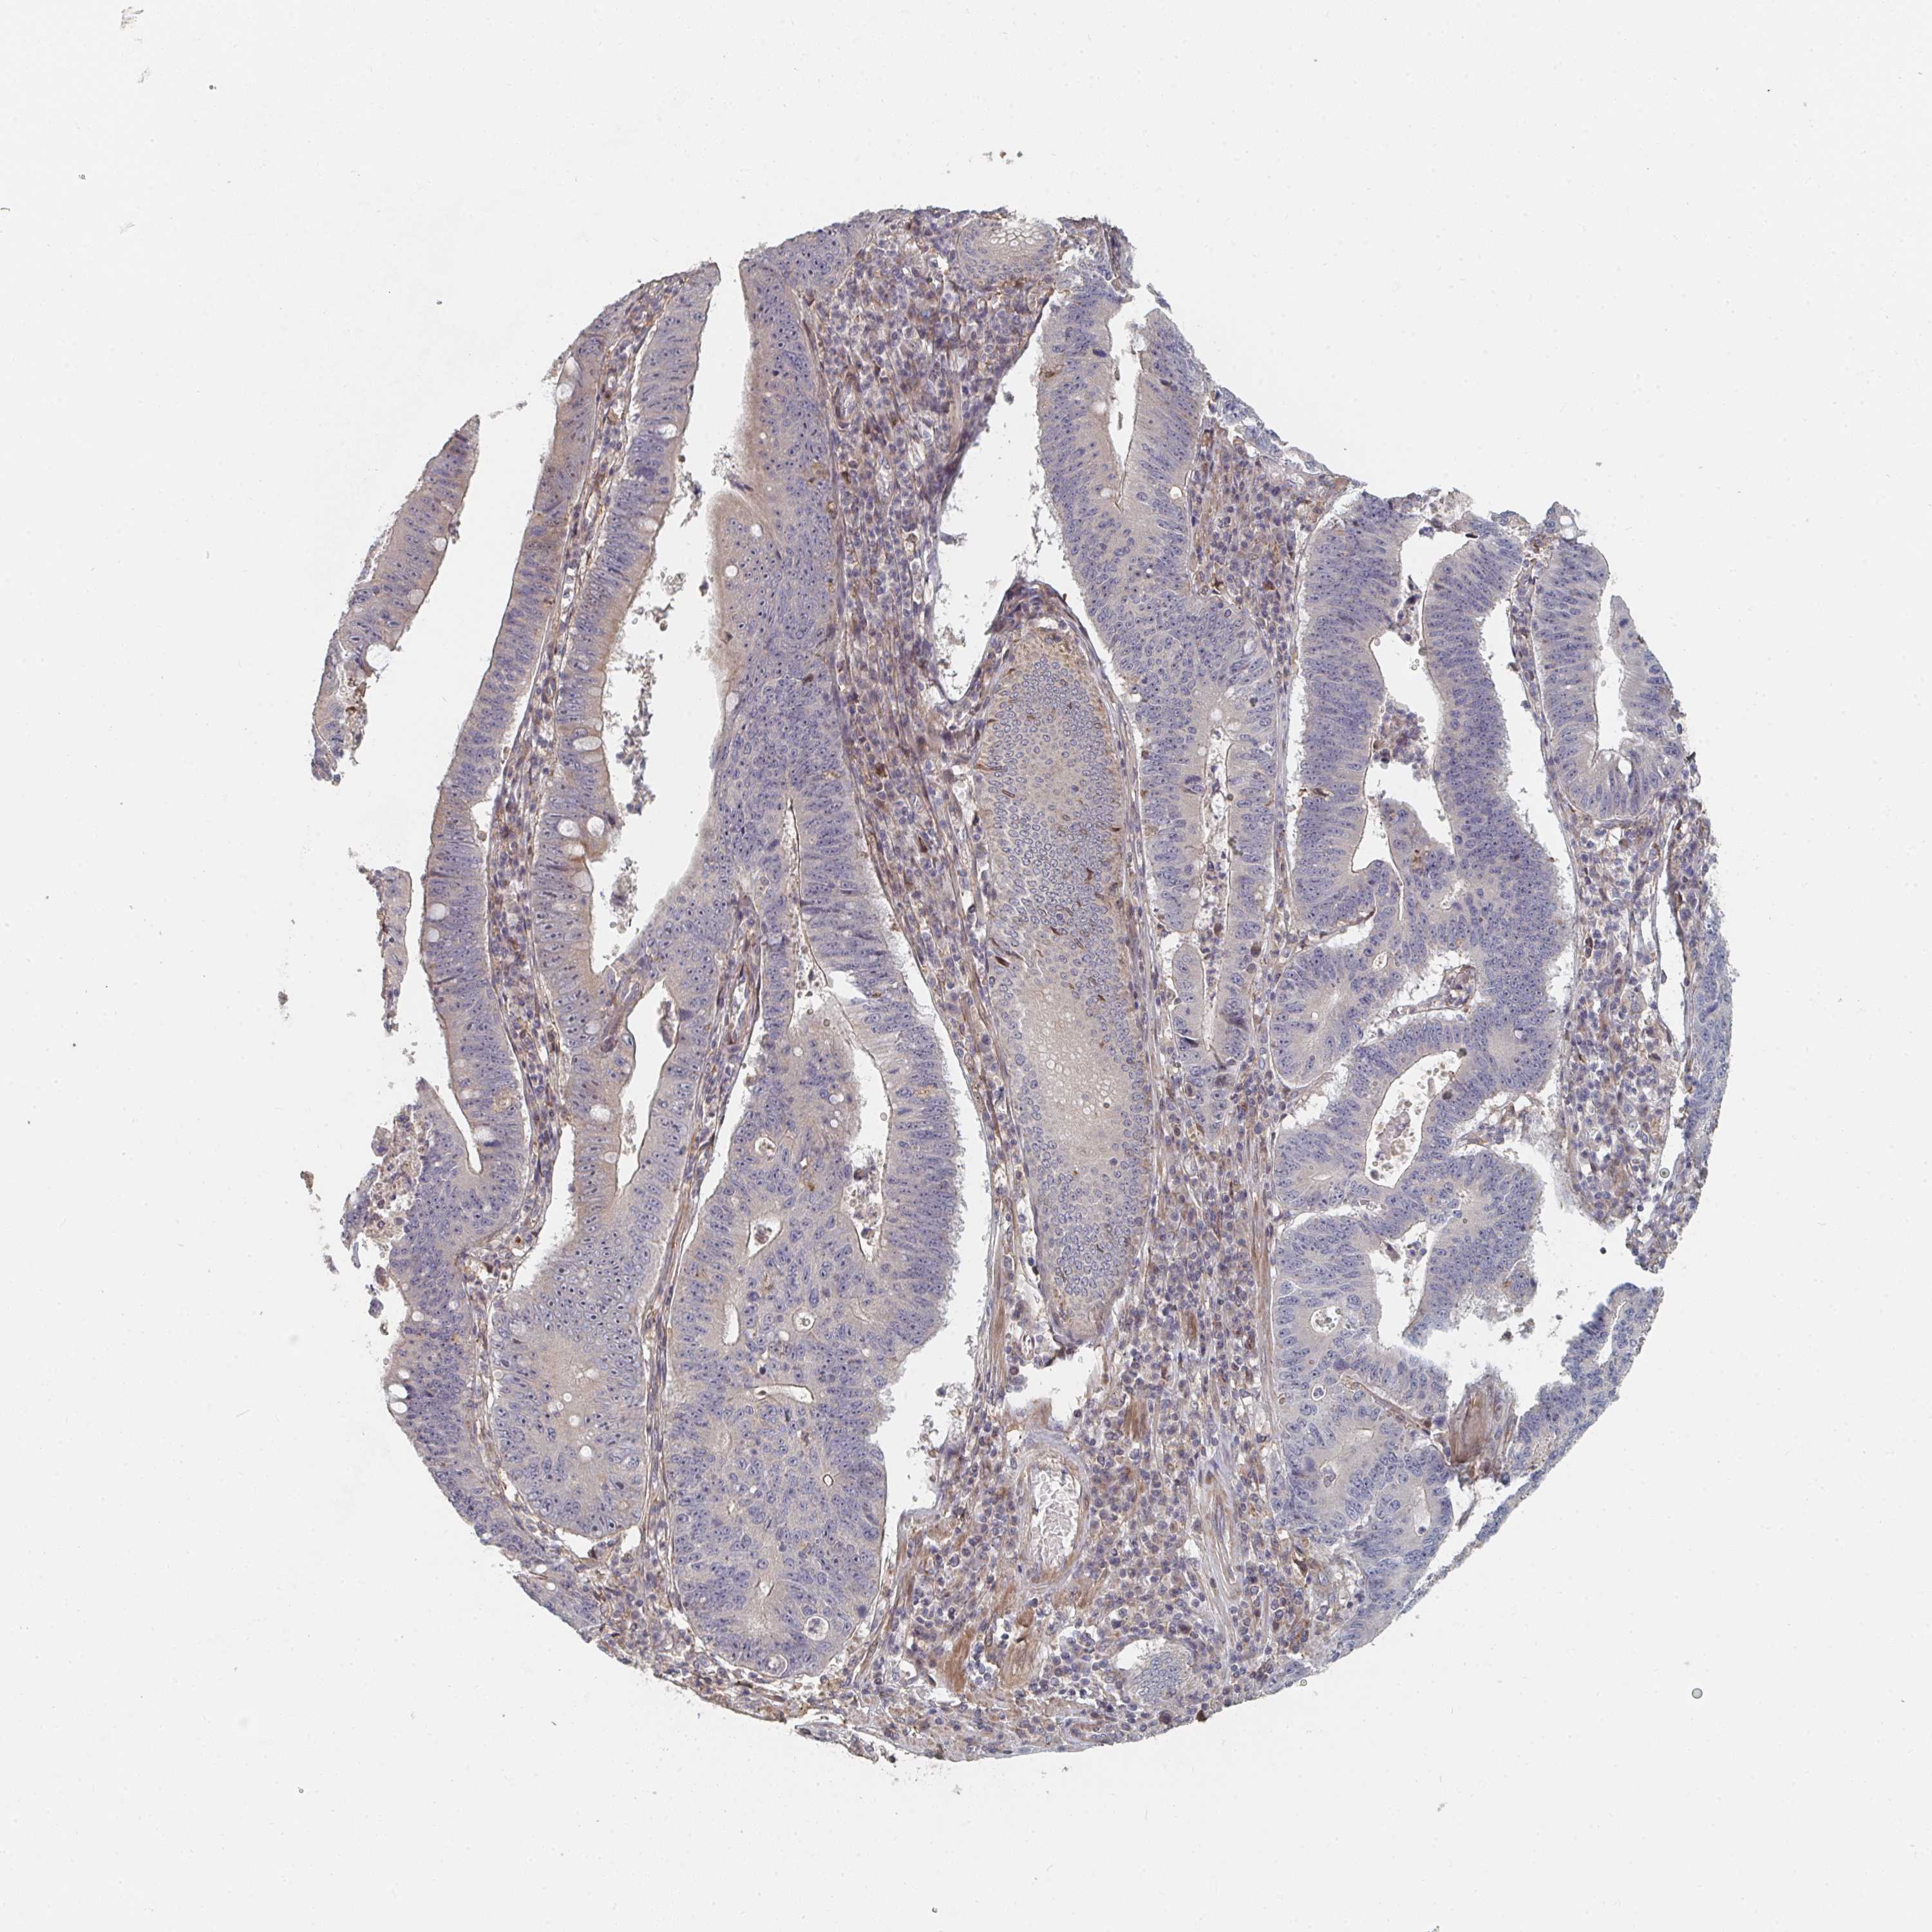

STOMACH CANCER - Protein expressioni

A mouse-over function shows sample information and annotation data. Click on an image to view it in a full screen mode. Samples can be filtered based on level of antibody staining by selecting one or several of the following categories: high, medium, low and not detected. The assay and annotation is described here.

Note that samples used for immunohistochemistry by the Human Protein Atlas do not correspond to samples in the TCGA dataset.

Antibody stainingi

Antibody staining in the annotated cell types in the current human tissue is reported as not detected, low, medium, or high, based on conventional immunohistochemistry profiling in selected tissues. This score is based on the combination of the staining intensity and fraction of stained cells.

Each image is clickable and will lead to virtual microscopy that enables deeper exploration of all samples and also displays staining intensity scores, fraction scores and subcellular localization as well as patient and tissue information for each sample.

Antibody HPA031335

Antibody CAB004076

Antibody CAB080153

Antibody CAB080157

Staining

High

Medium

Low

Not detected

Intensity

Strong

Moderate

Weak

Negative

Quantity

>75%

75%-25%

<25%

None

Location

Nuclear

Cytoplasmic/membranous

Cytoplasmic/membranous,nuclear

Adenocarcinoma, NOS

Adenocarcinoma, High grade